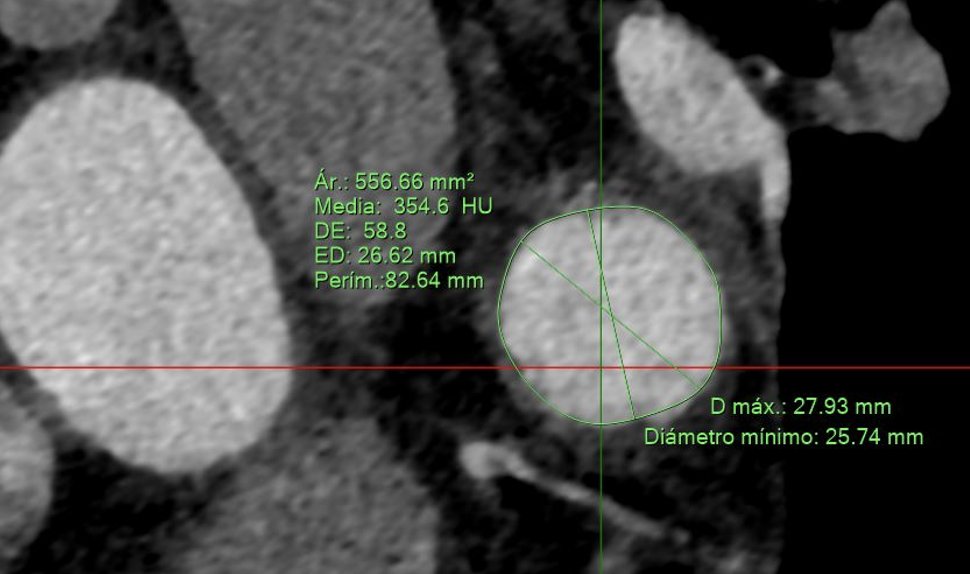

La versatilidad del dispositivo Watchman FLX permite cerrar orejuelas complejas como esta. Su pequeño tamaño supuso un reto pero finalmente conseguimos ocluirla con éxito. @GVAdsTorrevieja @CenturyRaul @bostonsci

0

11

19